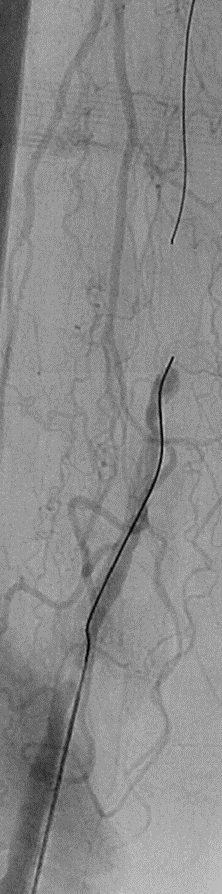

开通:以内膜下技术为主,逆穿是常用且有效的辅助手段。

预扩:充分预扩张至关重要,需逐级使用高压球囊,最终达到 6mm 直径,以获得足够的管腔。

支架植入:遵循“由远及近”原则,先放置远端 DES,再覆盖中段 VB,最后处理近端。利用 Eluvia 的可调节性优化重叠。

后扩:常规使用 6mm 高压球囊进行后扩张,确保支架充分贴壁和管腔获得。